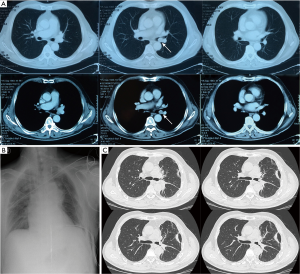

A 67-year-old man was admitted to our hospital in July 2012 complaining of hemosputum and chest pain. The patient accepted intravenous chemotherapy 4 times with paclitaxel and cisplatin before treatment in our clinic, and without any improvement in symptoms. Chest CT scan showed an intraluminal mass at the left main bronchus, the whole left lung was atelectasis (Figure 2A). Endobronchoscopy examination showed a papillary neoplasm bulge at the middle left main bronchial cavity in about 1 cm diameter, completely blocking the lumen. Biopsy revealed low-grade malignancy, tendency to adenoid cystic carcinoma. The basic surgical procedures in this patient were same as the first case, and the two-step anastomosis was performed between the left main bronchus and the ends of the left upper and lower bronchi, using 3-0 Vicryl sutured. The anastomosis was wrapped with the intercostal muscle pedicle flap at last. The unique procedure was that we had repeated lung lavage several times before anastomosis was performed, in order to identify the lung parenchymal was not infringed by lung abscesses and could be recruited during ventilation. The postoperative follow-up was over 2 years without recurrence of the tumor (Figure 2B,C).